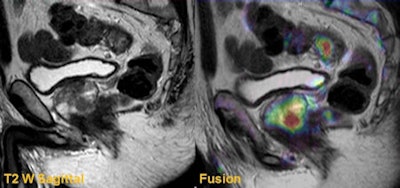

Differentiating the tumor from the rectal wall often is difficult on fast spin-echo (FSE) T2-weighted (T2W) imaging, he continued. In particular, a small, low rectal tumor can be challenging because of the contrast difference between the tumor and adjacent intrinsic and extrinsic sphincter complex. In such circumstances, DWI with high B-values plays a major role in identifying the tumor. Coregistering high-resolution T2W images with the DWI and apparent diffusion coefficient (ADC) map significantly increases the sensitivity of identifying the tumor.

High-resolution T2W imaging demonstrates detailed anatomy of the rectal wall, but due to low contrast between the tumor and the rectal wall, accurate staging can be difficult, he confirmed. On the B-value images, although the signal-to-noise ratio is low, the contrast between the high signal tumor and the rectal wall can be clearly demonstrated. Moreover, when the DWI is coregistered with T2W images, the T-staging can be performed with high accuracy.